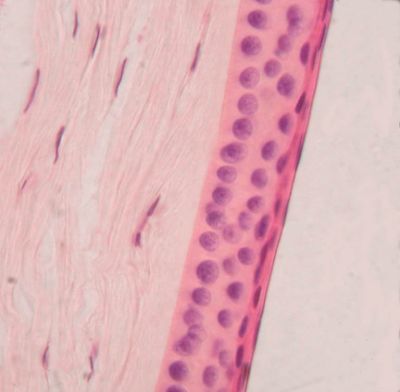

Cornea, monkey - histology slide

This is a histology slide of a monkey cornes. This slide shows the epihelium.

Histology slide courtesy of Florida State University.